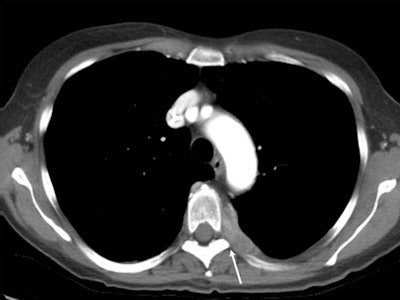

Tumor patients are a sensitive and highly specific group. The pain is usually very severe, cannot be controlled by analgesics, and is inaccessible to other procedures, so this is where interventional radiology comes in. With painful osteolytic processes, such as, for instance, bone metastases, we can carry out cementation and stabilization using minimally invasive access or we can destroy the tumor locally with CT-guided probes inserted into a painful area of tumor, and this is called ablation.

The most common procedure is thermal ablation, which "cooks" the tumor tissue. Thermal ablation can be used even with large tumors because it treats only that part of the tumor which is causing the pain. The effect is the patient is no longer aware of the pain, even if the thermal ablation cannot destroy the entire tumor.